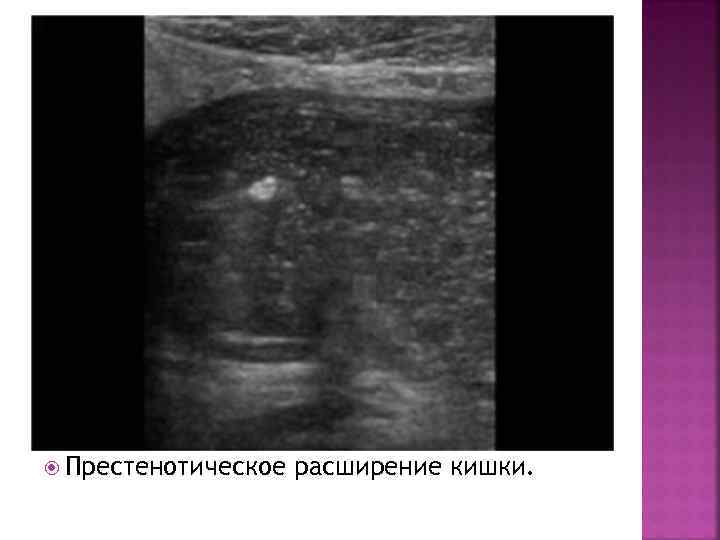

Престенотическое расширение кишки.